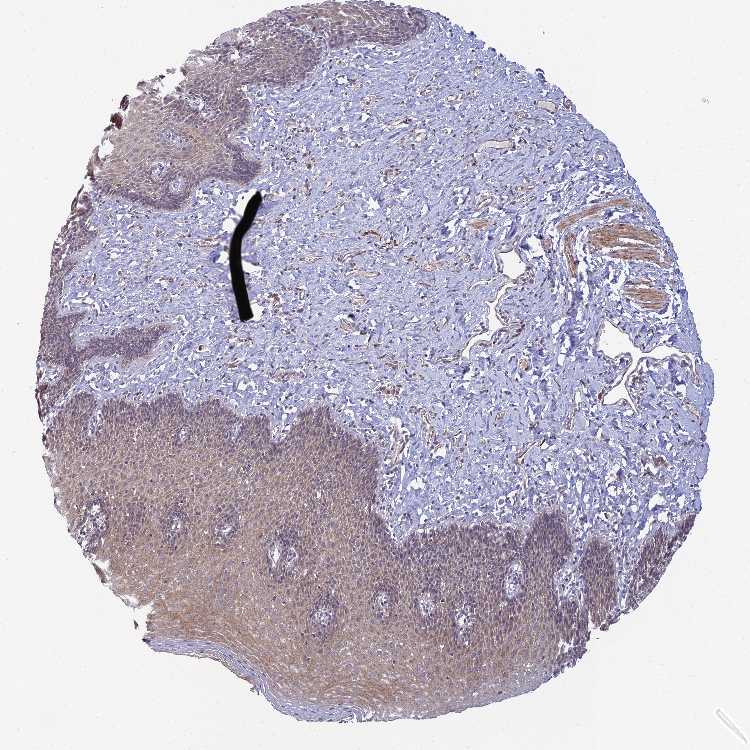

ESOPHAGUS - Antibody stainingi

Antibody staining in the annotated cell types in the current human tissue is reported as not detected, low, medium, or high, based on conventional immunohistochemistry profiling in selected tissues. This score is based on the combination of the staining intensity and fraction of stained cells.

Each image is clickable and will lead to virtual microscopy that enables deeper exploration of all samples and also displays staining intensity scores, fraction scores and subcellular localization as well as patient and tissue information for each sample.

Antibody HPA044572Antibody HPA056798Antibody CAB016733Antibody CAB034368

Squamous epithelial cells Not detectedNot detectedMediumNot detected